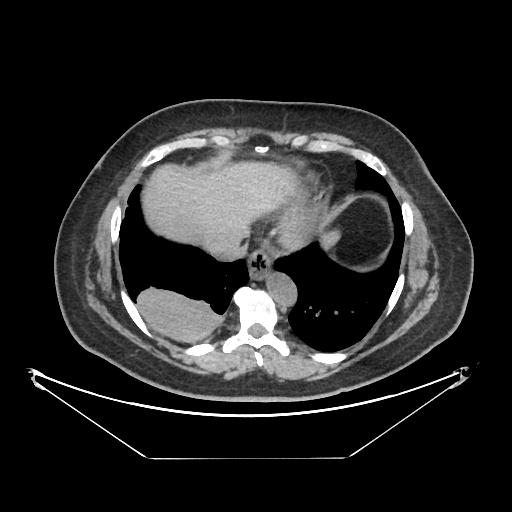

Image Grid

4Γ—3 grid: Rows show different image types (Original NATIVE, Reconstructed NATIVE, Original VENOUS, Generated VENOUS), Columns show windowing techniques (No Window, Lung Window, Mediastinum Window)

Generated VENOUS CT scan (A→B translation)

Full window (WL 1023.5, WW 4095 β†’ Low βˆ’1024, High +3071)

Lung window (WL -600, WW 1500 β†’ Low βˆ’1350, High +150)

Mediastinum window (WL 40, WW 400 β†’ Low βˆ’160, High +240)